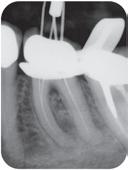

Ny, trådløs endomotor gir maksimal valgfrihet!

Nye Sendoline Endo Motor kan brukes med både roterende og resiprokerende filsystemer!

Stor valgfrihet! Bruk den bare som endomotor, som endomotor med apekslokator eller bare som lokator.

Vinkelstykket har slank, smal hals og et lite hode som kan roteres 360°. Dette gir deg enda bedre og enklere tilgjengelighet i munnen, med optimal sikt.

Rotary S5 System

Reciprocating S1 System

16.990,-